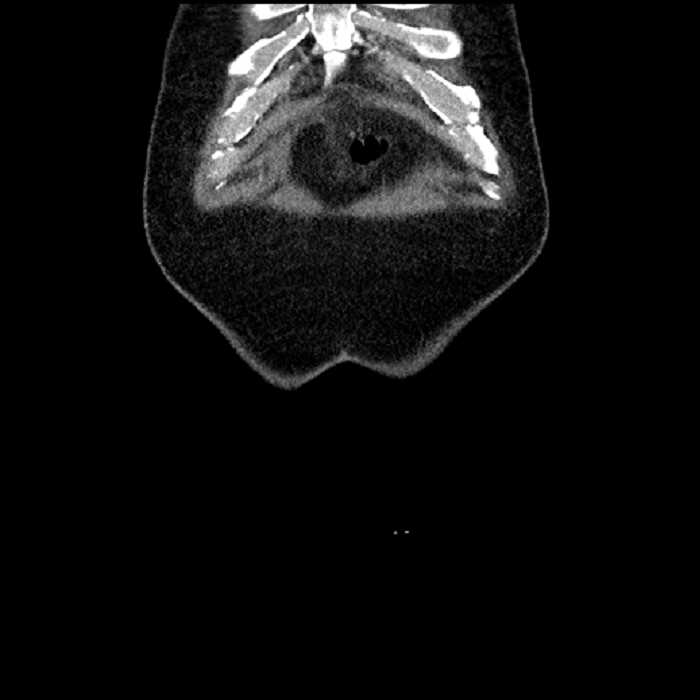

Age: 63

Sex: Male

Indication: Abdominal pain

• Ankylosis of both sacroiliac joints

Acute sigmoid diverticulitis complicated by a small contained perforation and a large abscess in the right hepatic lobe. Additional small subcapsular abscesses along the anterior margin of the left hepatic lobe.

Hepatic abscess showing the double target sign with low density internally surrounded by a thin inner enhancing rim (red arrow) and ill-defined outer low density rim (yellow arrow). Blue arrow indicates an internal septation. Red arrows: additional smaller subcapsular abscesses. Red arrow: focal contained perforation associated with diverticulitis.